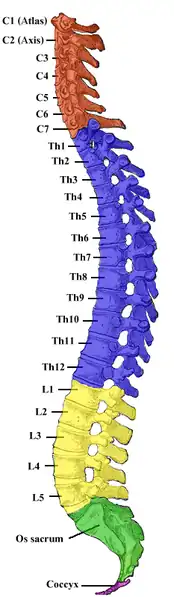

In human anatomy, the five vertebrae are between the rib cage and the pelvis. They are the largest segments of the vertebral column and are characterized by the absence of the foramen transversarium within the transverse process (since it is only found in the cervical region) and by the absence of facets on the sides of the body (as found only in the thoracic region). They are designated L1 to L5, starting at the top. The lumbar vertebrae help support the weight of the body, and permit movement.

Shape of lumbar vertebrae (shown in blue and yellow). Animation. Vertebral column.

Vertebral column

Vertebral column Illustration highlighting lumbar spine.